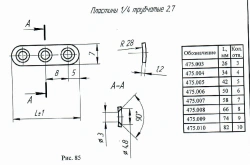

Non-Sterile Implantable Plate 1/4 Tubular 2.7, Article 475.003

US$9-30

Length:

26

Material:

Titanium alloy

OSTEOMED-M LLC 🇷🇺